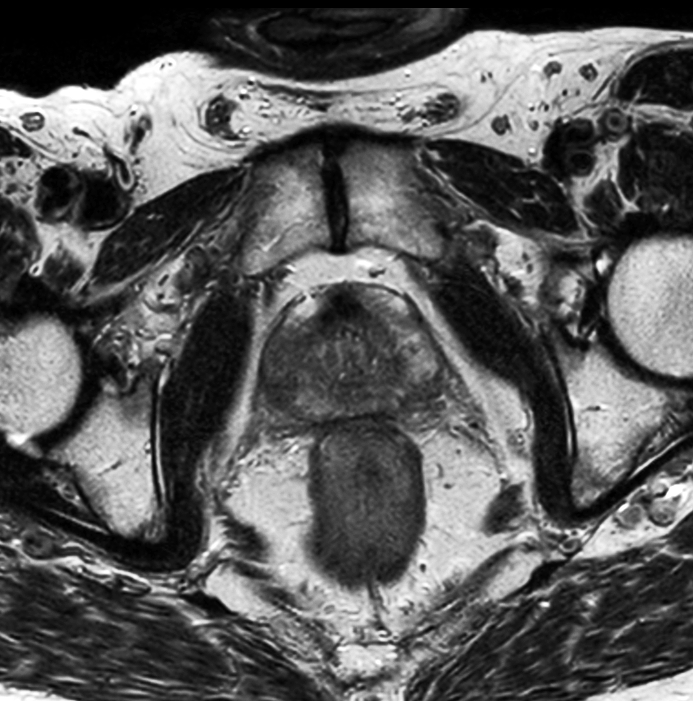

70-year-old male with prostate cancer, cT3bNxM, Gleason 6, PSA 7.9 mg/L, underwent MRI on Ingenia 3.0T MR-RT before radiation therapy, next to CT simulation. Patient was imaged at Ingenia MR-RT 3.0T using FlexCoverage Anterior Coil in combination with the integrated Posterior Coil.